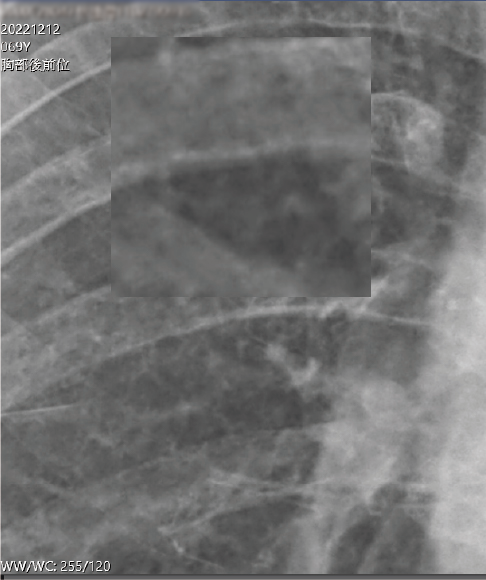

2022/12/12 林先生 69歲

施打外泌體前

1.兩肺纖維化

2.左肺門附近結節x2,約0.4公分

3.血氧濃度92%